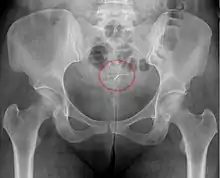

- A "lost coil" occurs when the thread cannot be felt by a woman on routine checking and is not seen on speculum examination.[58] Various thread collector devices or simple forceps may then be used to try to grasp the device through the cervix.[59] In the rare cases when this is unsuccessful, an ultrasound scan may be arranged to check the position of the coil and exclude its perforation through into the abdominal cavity or its unrecognised previous expulsion.